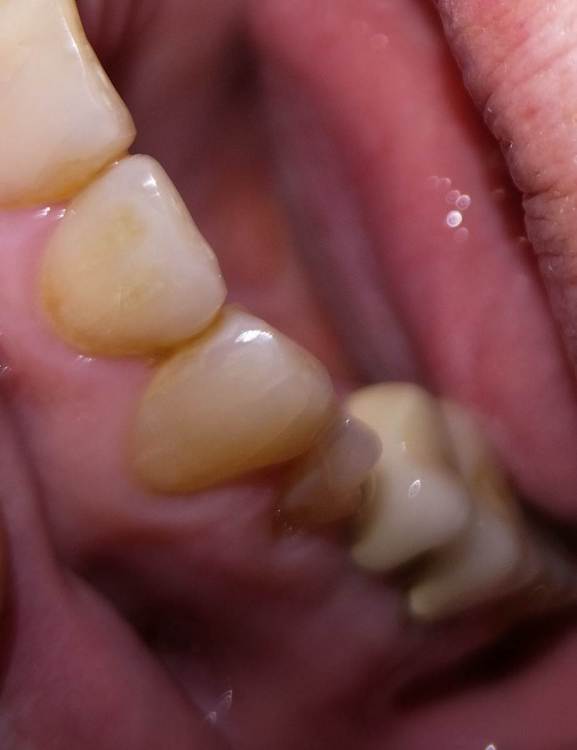

Dashik Опубликовано 16 июня, 2023 Поделиться Опубликовано 16 июня, 2023 Добрый день, уважаемые стоматологи! В середине августа 2021 года у моей мамы (сейчас 63 года) выпал мост. Была далеко от дома. Пришла приклеить мост, оказалось, что 5 зуб раскололся от штифта, его выдернули, у моста отрезали коронку на 3.7 зуб, приклеили, стоит до сих пор. В апреле решила заняться зубами. Хочет ставить имплантаты на месте вывалившегося моста. Была на двух консультациях. Кость позволяет, но волнуют некоторые несовпадающие сведения, полученные на консультациях. Хочет услышать третье мнение на волнующие её вопросы. 1. Что делать с 3.7 зубом? 2. Сильная ли произошла атрофия десны, и необходимо ли брать с нёба кусок слизистой для неё. Можно ли обойтись без этих манипуляций? Как-то всё-таки хотелось менее травматичный способ установки имплантатов. 3. В ноябре 2010 году были установлены 3 имплантата системы XIVE. Возможно ли сейчас при нашей ситуации установить такие же имплантаты, чтобы во рту была одна система? 4. Возможно ли ей установить имплантаты без разрезания десны безлоскутно? 5. Можно ли сохранить 1.4 зуб на верхней челюсти? Там была большая пломба, которая отвалилась с частью зуба. 6. Кт было сделано 5 апреля, сколько ещё есть времени (если оно ещё есть) на поиски врача-импантолога, чтобы не облучаться повторно? Фото зубов, ортопантомограмма и кт зубов прилагаются. Правда, я не очень уверена в правильном развороте зубов, крутила-крутила пол дня. Если не информативно, попробую сделать в другом ракурсе. Заранее очень благодарна за ответы и потраченное время. Большое спасибо! Ссылка на комментарий

Irouil Опубликовано 16 июня, 2023 Поделиться Опубликовано 16 июня, 2023 1. Он как-то беспокоит? 2. Сильная, мягкотканная аугментация показана 3. Наверное возможно, но зачем? 4. Нет, см. пункт 2 5. На первый взгляд - нет, но надо рассверлить зуб и посмотреть прямым взглядом 6. Сколько угодно, да и от КЛКТ облучение незначительное Ссылка на комментарий

Irouil Опубликовано 18 июня, 2023 Поделиться Опубликовано 18 июня, 2023 @Dashik Сравнивать надо не мерседес и хендэ, а такси мерседес и хендэ. Ибо вы не покупаете автомобиль, а покупаете поездку на нем - услугу по оказанию медпомощи. И навыки водителя+состояние автомобиля тут гораздо важнее, чем его марка. Правило всегда одно - самый простой (дешевый/ненадежный) имплант в умелых руках намного лучше работает, чем самый хороший - в неумелых. Два лучше ставить потому, что чем меньше дырок в человеке - тем лучше. Есть важные уточняющие факторы (предельные размеры имплантов, протяжённость протеза), но в конкретно представленной ситуации я с большой долей вероятности все равно бы больше двух не установил. Если там действительно перелом, то зуб будет вызывать воспаление окружающих тканей и со временем заставит себя удалить. Надо регулярно осматривать полость рта у стоматолога, делать рентген снимки, но это нормальная профилактика и здоровых пациентов Ссылка на комментарий

annda Опубликовано 2 июля, 2023 Поделиться Опубликовано 2 июля, 2023 Трещин на КТ не видно, слишком тонкая структура. Линия перелома, да, видна, но крутить для этого не надо, она , как правило, видна явно. Для определения трещин есть другие признаки. Определенная форма кармана около трещины и сам этот карман в реальности, который зондируется специальным пародонтологическим зондом.Либо раскрывать зуб и смотреть корень под микроскопом, красить его специальной краской, чтобы трещину прокрасить явно. 1 Ссылка на комментарий